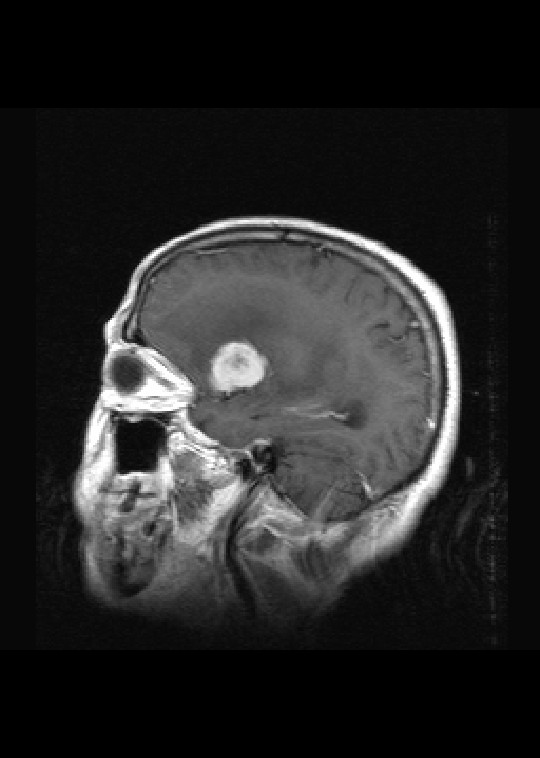

标题: MRI2527:脑部肿瘤,(病理结果:淋巴瘤)

(左额颞叶)非霍奇金淋巴瘤,b细胞性,弥漫性大b细胞型。免疫组化结果:cd45(lca) +,vimentin +,ck(ae1/ae3) -,ema -,cd3 -,cd20 +++,cd30 -,plap -,cd79a +,gfap -,alk -,s-100 -。

左侧基底节区病灶t1wi呈不均匀稍低信号,t2wi呈稍高信号,周围伴有水肿。增强扫描呈均匀团块样或者抱拳样明显强化,相邻的柔脑膜亦见线样强化。首先考虑淋巴瘤。可惜没有ct平扫,如果ct平扫病灶呈高密度,那么更支持pcnsl的诊断。

病理结果:(左额颞叶)非霍奇金淋巴瘤,b细胞性,弥漫性大b细胞型。免疫组化结果:cd45(lca) +,vimentin +,ck(ae1/ae3) -,ema -,cd3 -,cd20 +++,cd30 -,plap -,cd79a +,gfap -,alk -,s-100 -。

左侧基底节区病灶t1wi呈不均匀稍低信号,t2wi呈稍高信号,周围伴有水肿。增强扫描呈均匀团块样或者抱拳样明显强化,首先考虑淋巴瘤。